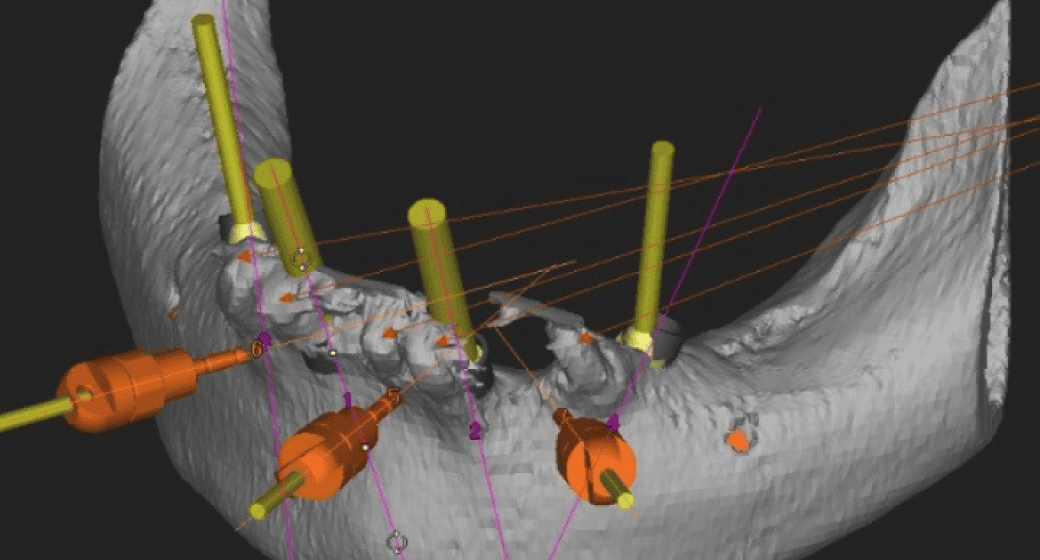

当院では、CT撮影による3D画像診断をもとに、骨の厚みや高さ、密度を立体的に把握。必要があれば、骨造成を取り入れたインプラント治療計画をご提案しています。

代表的な再生療法のひとつが「GBR(骨誘導再生法)」です。骨が不足した部位に自家骨や人工骨を補填し、特殊な膜(メンブレン)で覆うことで、骨の再生を促しインプラントの土台を築く方法です。

また、上顎奥歯など骨が特に薄い部位には「サイナスリフト(上顎洞底挙上術)」が適応されます。上顎洞と呼ばれる空洞の底を持ち上げ、その下に骨を造成することで、十分なインプラント埋入スペースを確保することが可能になります。

これらの高度な再生治療は、歯科用CTや精密シミュレーション技術、そして確かな経験を持つ術者による対応が前提となります。